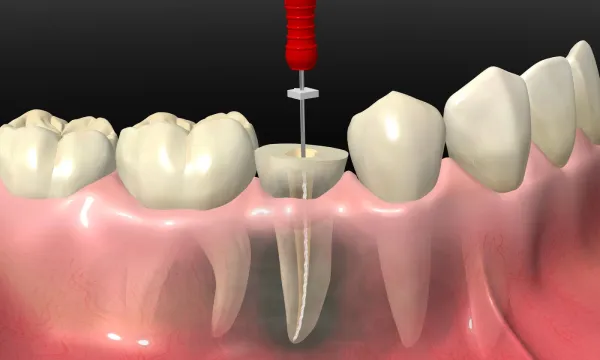

神経をとる治療

不幸にして神経をとらなければならなくなった場合は、神経が回復不可能、つまり死ぬ方向に進んでしまった場合に行います。まず、健全な歯の部分はなるべく削らず、更に根の治療が効率的に出来るように形成します。すると神経の上の部分がまず露出します。この部分は髄室といいます。 この部分の神経をしっかりとれるように角の部分(髄角)までしっかり形を作ります。その後、その下にある根の部分の神経の入り口(根管口)を探します。歯の種類に種類によって大まかな数は決まっていますが実際にはそれより多いことが多いので顕微鏡を使って慎重に探索し、取り残しのない様にします。 根管口が見つかったら神経を根の先まで探索し神経を除去します。神経はまっすぐなことはないので、途中で曲がった道に追従できずに進まなくなったり、また誤って別の道を作ったりしないように慎重に行います。

こうして根の先まで器具が到達したら、根の長さを測りそこまで神経の管を削って拡張するようにして腐敗物をきれいにし、さらに根の中に入れる最終的な詰め物が充填できるように形を整えます。 神経をとる治療は結局神経を根の中で一番細く治りやすいところで切っている治療なので必ず炎症が起きます。そこで、だいたいの拡大が出来たらケースバイケースで薬を貼薬します。 次回来院時、炎症が消退していたら神経の入っていたトンネルの空間を埋める治療に入ります。空間が残っていると体液の貯留が起こって炎症が生じるからです。このつめる行為を根管充填といいます。根管充填には、滅菌されたゴムをつめる方法と練り薬をつめる方法があります。いずれにしても、薬は空間を残さずにしっかり埋め安定していることが求められます。